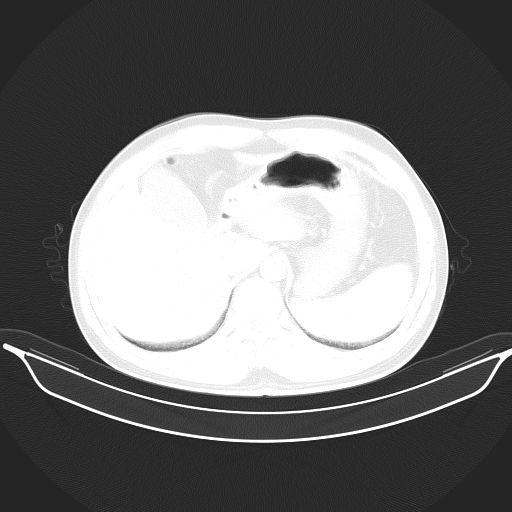

标题: CT25490:男,40岁,体检发现;无其它不适。 [打印本页]

标题: CT25490:男,40岁,体检发现;无其它不适。

考虑:1、过各敏性肺炎可能性大,建议定期复查。

2、轻度脂肪肝。